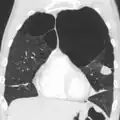

A chest X-ray is not useful to establish a diagnosis of COPD, but it is of use in either excluding other conditions or including comorbidities such as pulmonary fibrosis and bronchiectasis. Characteristic signs of COPD on X-ray include hyperinflation (shown by a flattened diaphragm and an increased retrosternal air space) and lung hyperlucency.[5] A saber-sheath trachea may also be shown that is indicative of COPD.[111]

A CT scan is not routinely used except for the exclusion of bronchiectasis.[5] Pulse oximetry measurement of peripheral oxygen saturation is recommended in people with clinical signs of respiratory failure or right heart failure.[5] An analysis of arterial blood is recommended in those with a peripheral oxygen saturation of 92% or less to determine actual blood oxygen level and assess for high levels of carbon dioxide in the blood, which may have therapeutic implications such as need for non-invasive ventilation or oxygen supplementation.[10] WHO recommends that all those diagnosed with COPD be screened for alpha-1 antitrypsin deficiency.[40]

Chest X-ray demonstrating severe COPD, displaying small heart size in comparison to the lungs

A lateral chest X-ray of a person with emphysema, displaying barrel chest and flat diaphragm

A severe case of bullous emphysema -

Axial CT image of the lung of a person with end-stage bullous emphysema -

Very severe emphysema with lung cancer on the left (CT scan)